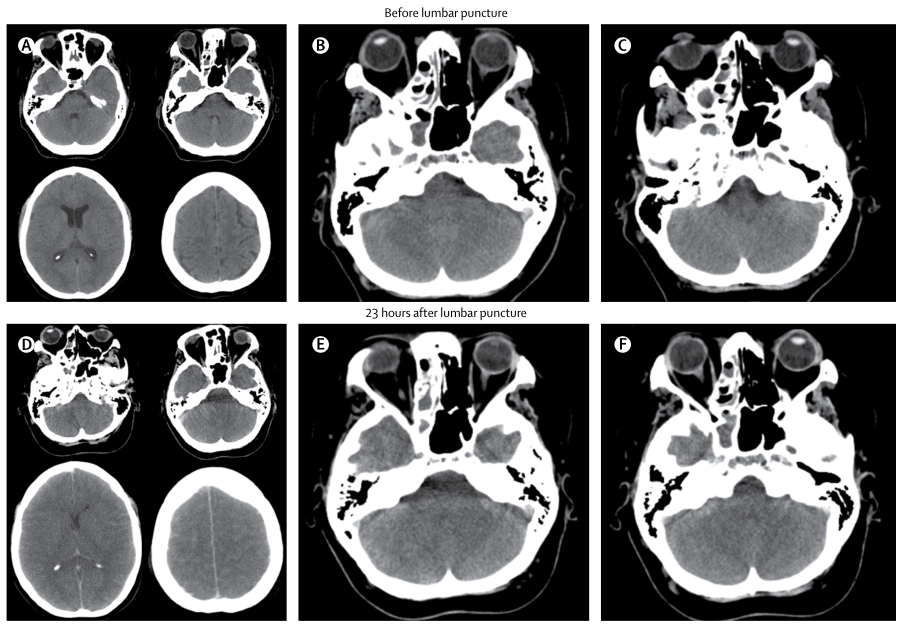

CT 上的脑移位和基底池闭塞的弥漫性脑水肿是腰椎穿刺的禁忌症(图 1)。新发癫痫、严重免疫受损状态、局灶性神经功能缺损或中度至重度意识障碍(GCS 分数 < 10)的患者在腰椎穿刺前应进行头颅 CT 检查 。

图 1. 细菌性脑膜炎患者腰椎穿刺前后颅脑 CT 上的弥漫性水肿

注:A. 弥漫性水肿和脑积水;BC. 基底池部分闭塞;D. 显示水肿增加;EF. 显示基底池完全闭塞和通过枕骨大孔的脑疝